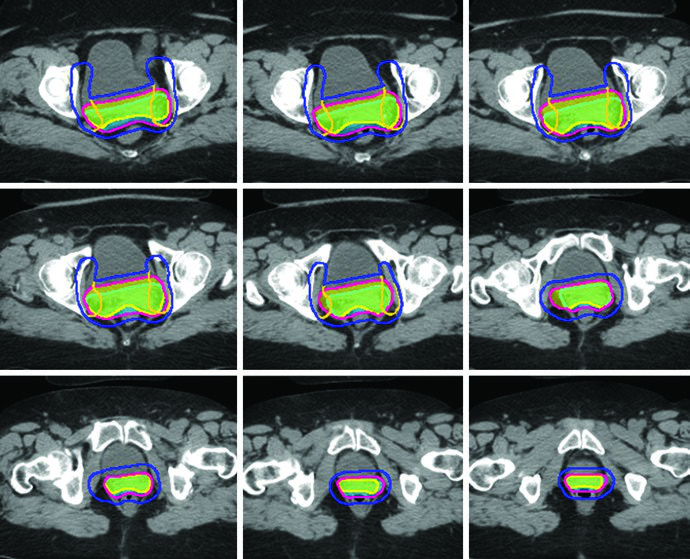

Final PTV Composition

PTVs are created for each CTV with different margins — 15 mm for CTV1, 10 mm for CTV2, and 7 mm for CTV3 — reflecting the degree of internal organ motion and setup uncertainty for each component. The final PTV for treatment planning is generated by combining the individual PTVs: PTV = PTV1 ∪ PTV2 ∪ PTV3.

When using the ITV approach, CTV1 and CTV2 should be contoured on both empty and full bladder scans and fused to generate the ITV. A 7 mm expansion on the ITV generates the PTV, which is combined with PTV3 for the final PTV. This strategy is particularly important because the vaginal cuff and paravaginal tissues undergo significant displacement with bladder filling variations.